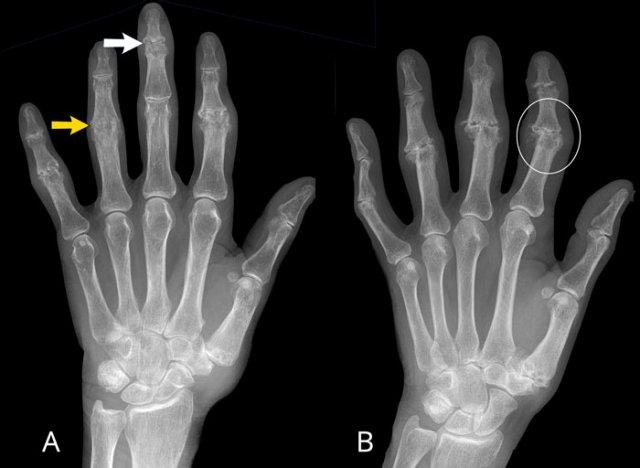

A

Tổn thương ăn mòn tại các khớp PIP 2-5 và DIP 3-5.

Biến dạng cánh hải âu điển hình tại DIP 3 (mũi tên trắng).

Dính khớp PIP 4 (mũi tên vàng), xuất hiện ở giai đoạn muộn của bệnh.

B

Hẹp khe khớp kèm ăn mòn trung tâm. Biến dạng cánh hải âu tại PIP 2-4, DIP 2 và khớp CMC-1.

Dính khớp DIP 3. Lệch trục về phía trong của PIP 2.